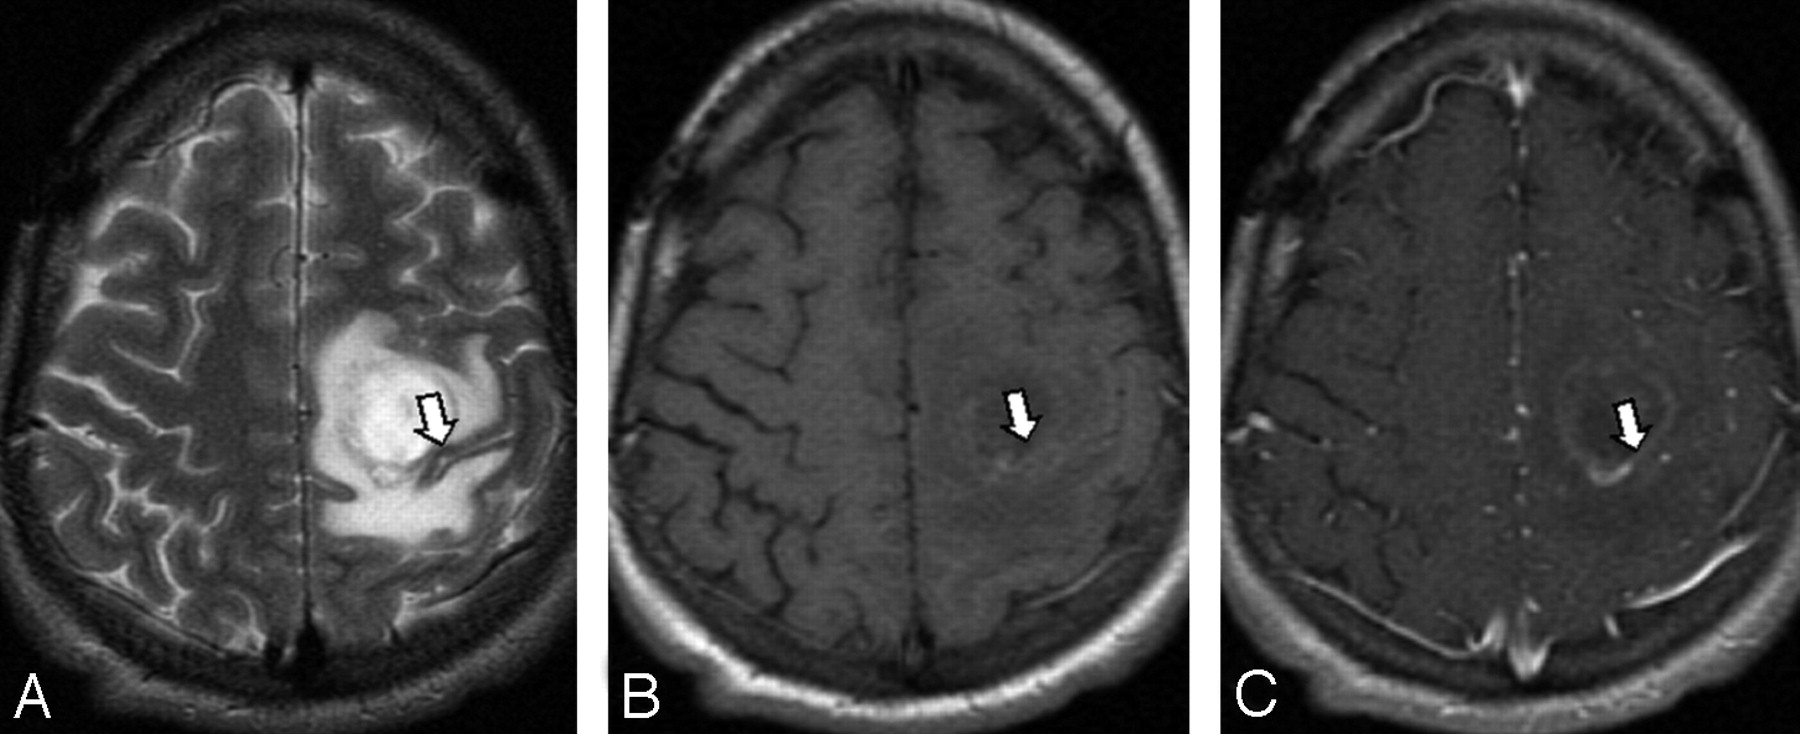

Differential cortical thickness across the central sulcus was readily visible on T2-weighted sequences in the presence of vasogenic edema (Fig 1). Minimal difference in cortical thickness was observed across neighboring parietal and frontal sulci (Fig 1). This visual impression was confirmed by direct measurement. Identification of the central sulcus was obscured on the corresponding T1-weighted images because of mass effect and sulcal effacement (Figs 2 and 3).

A metastasis adjacent to the motor strip (arrow), confirmed by intraoperative cortical mapping. The motor cortex is thicker than the sensory cortex on T2-weighted imaging (A). This is not apparent on T1-weighted precontrast (B) and postcontrast (C) images in which the sulci are effaced.